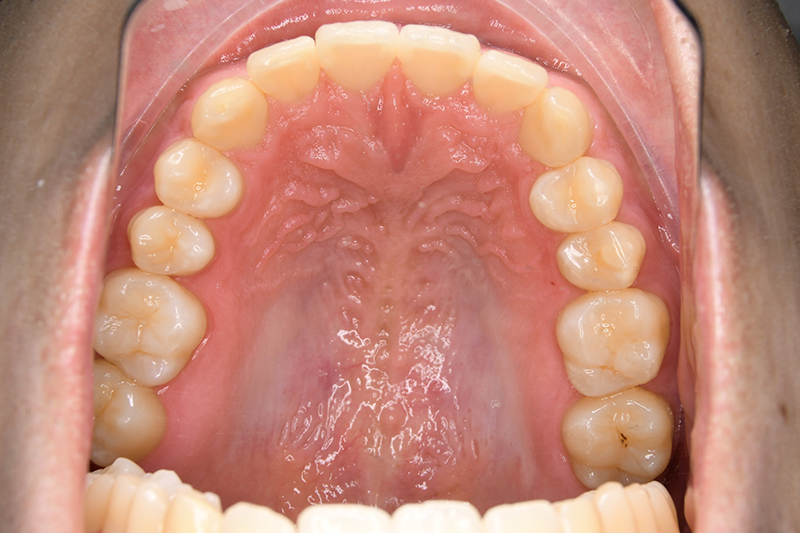

動的治療終了時

FP・IOP

口腔内所見 over jet 8.5mm、over bite 6.0mm、下顎前歯先天欠如、右側臼歯関係I級、左側II級(end on)、上顎歯列弓はオーボイド型なのに対して、下顎は狭窄歯列、叢生歯列弓を呈しており左側は鋏状咬合となっていた。

批評・予后 左側臼歯uprightによって鋏状咬合、過蓋咬合の改善が得られた。下顎前歯先欠によるAnterior ratio不調和と上顎前歯部叢生の改善を目的とし、上顎前歯にIPRを行ったが、治療後において左上2付近のover jetが大きく、上顎犬 歯間幅径の拡大(1.5mm)も生じているため、後戻りの懸念が残る。口元や歯列の安定性を考慮し、小臼歯抜歯も検討したがハイアングルであり下顎3-incisalのため、治療が困難となる事を危惧して非抜歯にて治療を行った。